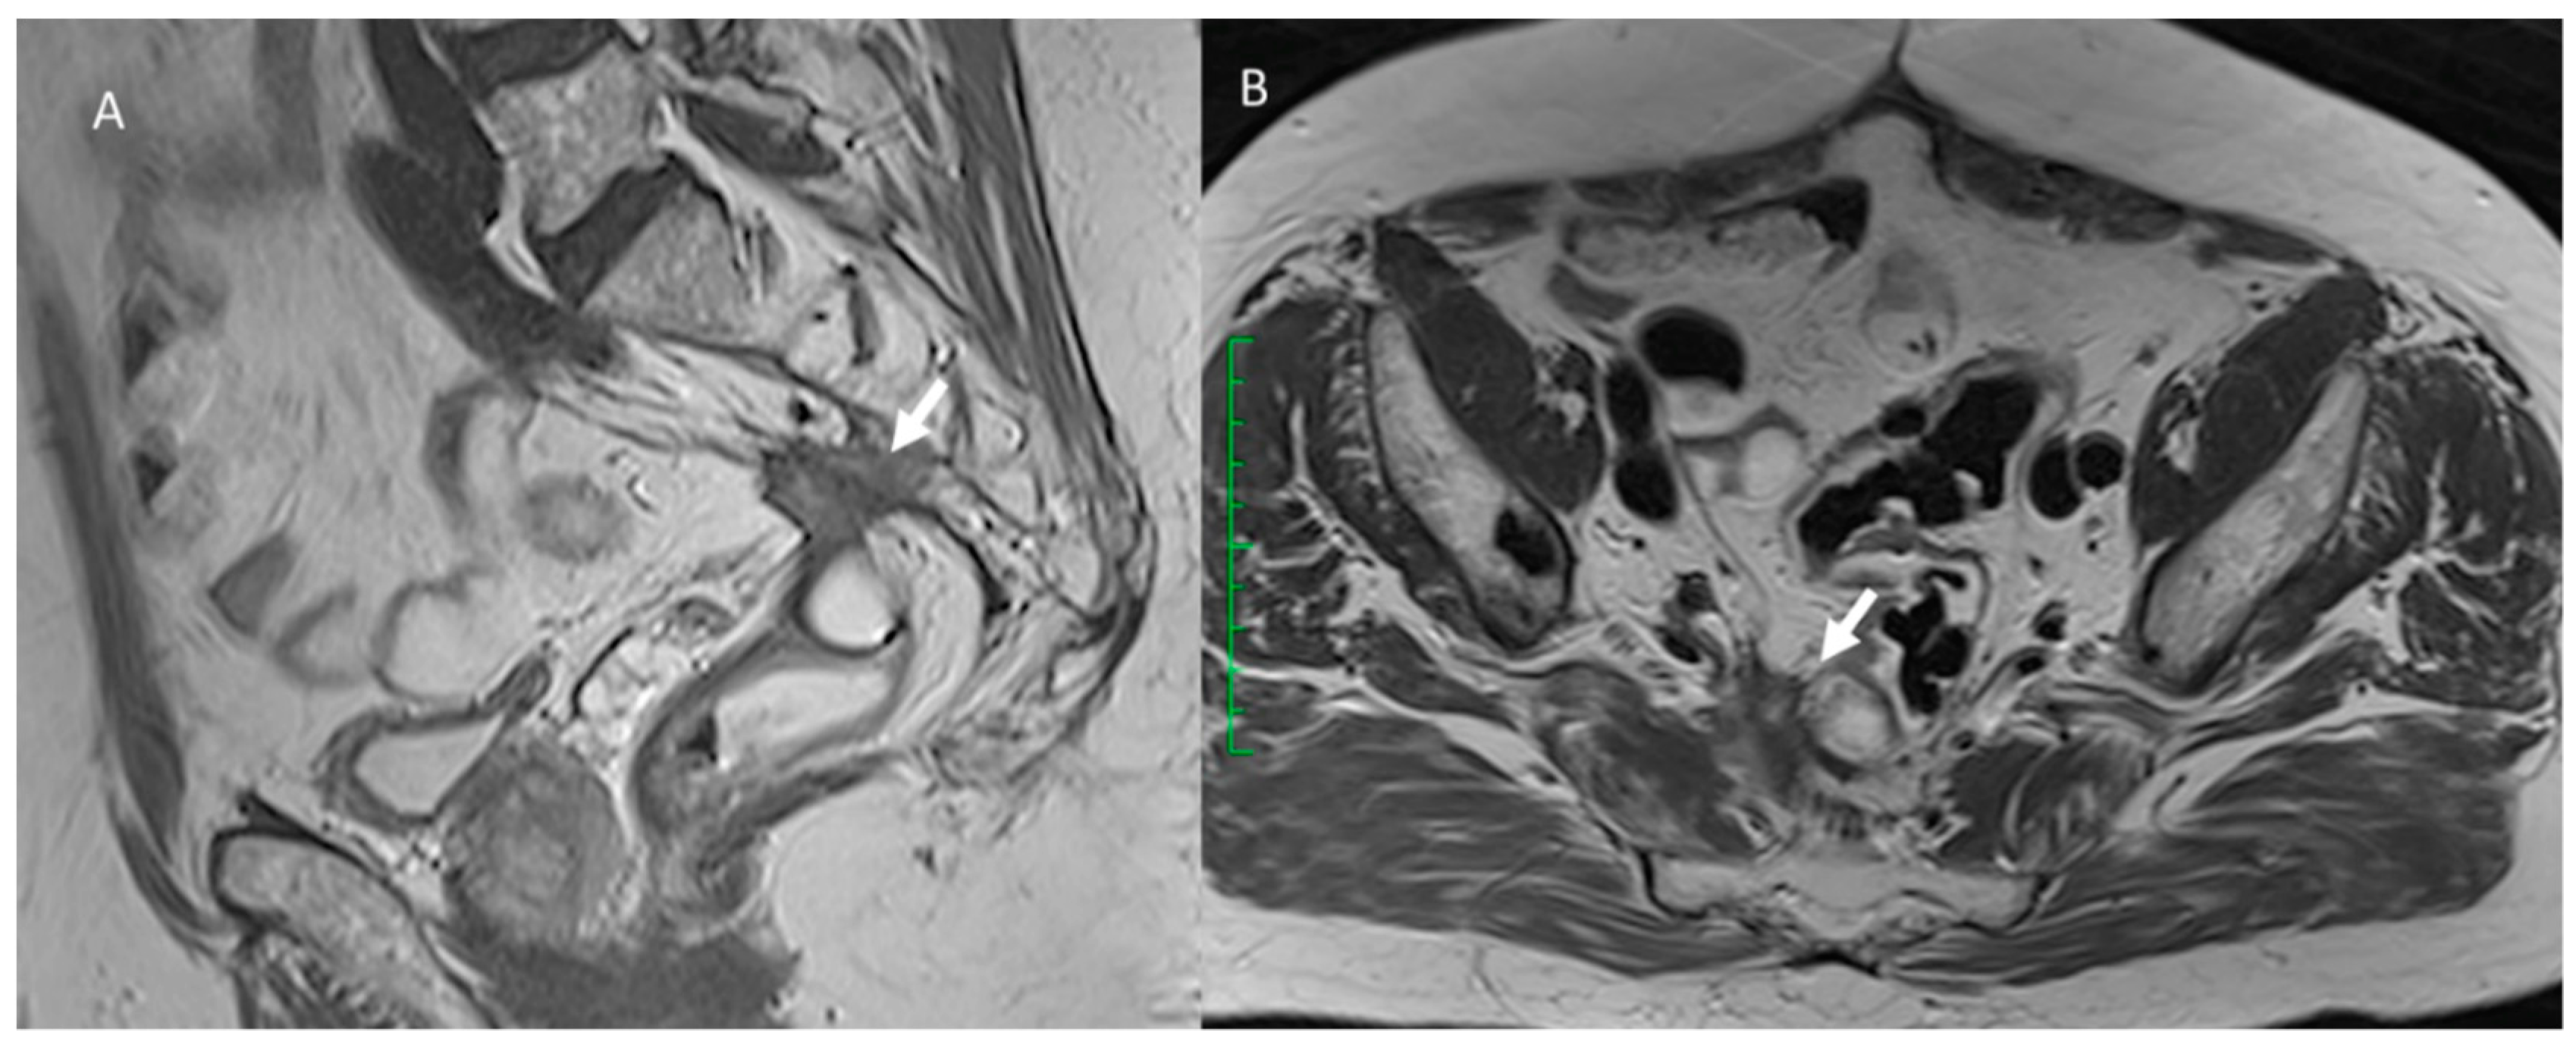

3.2. Fistula

3.3. Bleeding